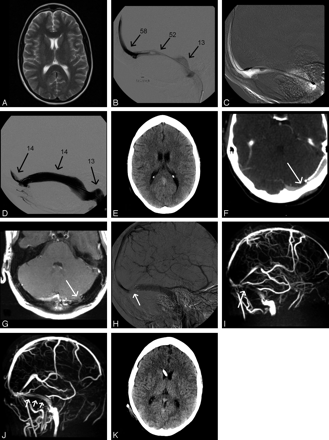

Bilateral papilledema and elevated lumbar CSF pressure (30 cm H2O) were observed in a 31-year-old woman (143 kg) with almost complete loss of vision in both eyes and worsening of headaches. MR imaging showed dilation of both optic sheaths and a flattened pituitary (Fig 3A), consistent with increased intracranial pressure. TS stenoses were suspected on MRV. Headache almost resolved after lumbar puncture, and vision improved. A lumbar drainage was used lowering CSF pressure to 11 cm H2O. MR imaging/MRV showed signs of intracranial pressure reduction (Fig 3B) and a decrease of venous stenoses. Venography was performed to exclude relevant hemodynamic stenoses (Fig 3B). We clinically monitored the natural course of the disease for 7 days, during which vision remained stable. Despite the benign clinical course, follow-up MR imaging showed re-occurrence of pressure signs (Fig 3C). Finally, ventriculoperitoneal shunt surgery was performed. Six months after dismissal, the patient was still free of headache. Vision had improved slightly.

A–C, Case 3: MR imaging, MRV, and conventional venography at different points of time. CSF pressure 30 cm H2O (A); after CSF diversion, pressure of 11 cm H2O (B); and 7 days later (C). Fat-saturated T2-weighted turbo spin-echo inversion-recovery images in the coronal plane (TR/TE, 2650/180; Sl, 3 mm) (i), showing widening of the optic sheathes in A and C (arrows) and partially empty sella in A (ii) and C (ii). MIP of MRV in oblique anteroposterior views demonstrating narrowing of the RTS (iii) and the LTS (iv) (arrows) as well as in the straight sinus (arrowheads). T2-weighted turbo spin-echo images in the axial plane at the level of the straight sinus (arrows) and superior sagittal sinus (arrowheads, v), both being compressed in C. T2-weighted axial images showing normal ventricle size (vi). Conventional venography with the catheter placed in the RTS close to the torcular herophili was performed after CSF diversion (pressure of 11 cm H2O). B vii, Anteroposterior view shows bilateral low-grade TS stenoses. B viii, Lateral tilted view shows intravenous pressure monitoring in the RTS at different locations (arrows, pressure in centimeters H2O).